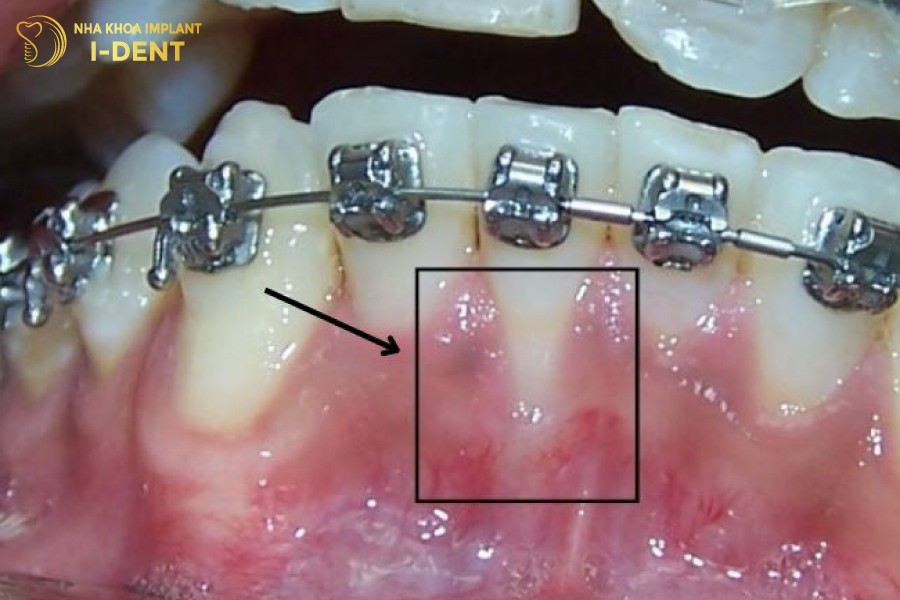

2.1 Tụt nướu (lợi) chân răng

Khi xương hàm bị tiêu đi, dẫn đến việc không còn đủ khả năng hỗ trợ mô nướu. Điều này có thể dẫn đến hiện tượng tụt lợi chân răng. Khi nướu giảm xuống, phần viền nướu trở nên mỏng và làm cho chân răng trở nên rõ ràng hơn so với trạng thái bình thường.

Tụt nướu